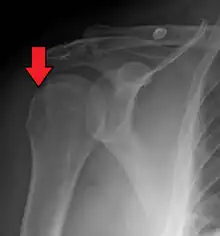

![]() | |

| Anterior shoulder dislocation on X-ray with a large Hill–Sachs lesion | |

A Hill–Sachs lesion, or Hill–Sachs fracture, is a cortical depression in the posterolateral head of the humerus. It results from forceful impaction of the humeral head against the anteroinferior glenoid rim when the shoulder is dislocated anteriorly.

Diagnosis can be suspected by history and physical examination which is usually followed by imaging. Because of the mechanism of injury, apprehension of anterior dislocation is common with provocative maneuvers. Hill–Sachs lesions have been classified as "engaging" or "non-engaging", with engaging lesions defined by the ability of the glenoid to sublux into the humeral head defect during abduction and external rotation. Engaging dislocations have a higher risk of recurrent anterior dislocation, and their presence can help guide surgical management.[2] Imaging diagnosis conventionally begins with plain film radiography. Generally, anteroposterior (AP) radiographs of the shoulder with the arm in internal rotation offer the best yield while axillary views and AP radiographs with external rotation tend to obscure the defect. However, pain and tenderness in the injured joint make appropriate positioning difficult and in a recent study of plain film x-ray for Hill–Sachs lesions, the sensitivity was only about 20%. i.e. the finding was not visible on plain film x-ray about 80% of the time.[3]